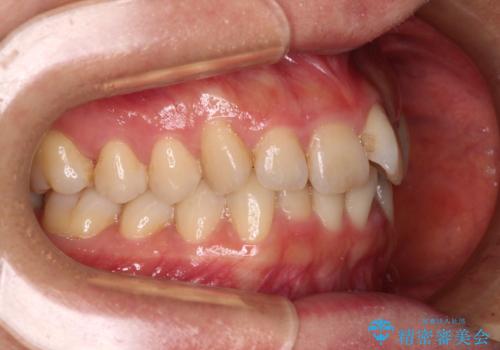

- 上下前歯のデコボコを気にして来院された患者様です。

叢生は軽度で、ワイヤー矯正でもマウスピース矯正でも対応可能な歯列でした。

僅か1年間できれいに歯列を整えることができ、患者様には大変満足していただきました。